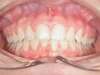

Chevauchement sévère. Traitement multibague sans extraction.

Avant

Après